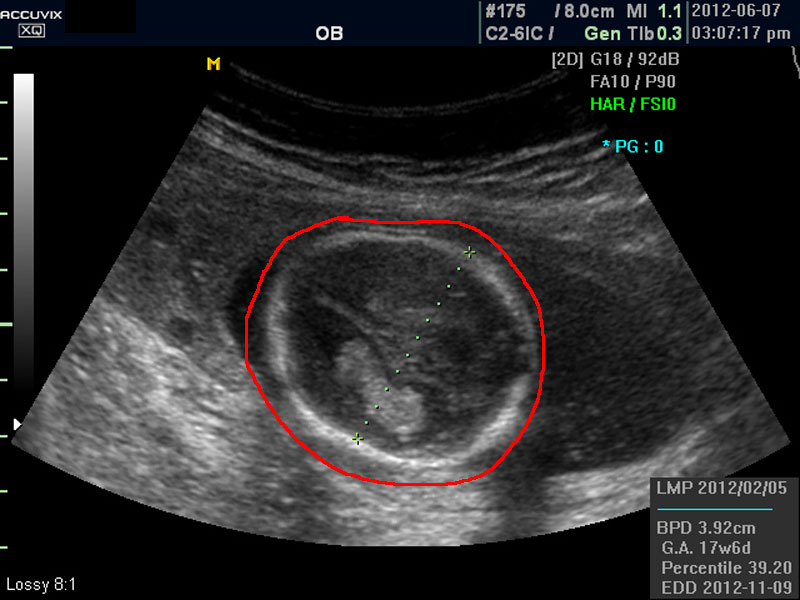

위 사진에서 빨간 동그라미로 표시한 부분이 태아의 머리를 위에서 내려다 본 수평 단면입니다.

하얗게 보이는 것은 뼈이고 내부에 검게 보이는 것은 뇌실에 고인 척수액 부분이며 내부의 하얀 부분은 뇌조직과 뇌실 내 맥락막이라고 하는 것입니다.

모든 사진에서 우측 하단에는 기본적인 발육 정보가 기록되는데 세번째 사진에서 빨간 펜으로 표시한 부분이며 그 내용의 의미는 아래와 같습니다.

4. BPD

Biparietal Diameter의 약자로 머리를 위에서 보아서 양쪽 옆통수에서 반대쪽 옆통수까지의 길이입니다.

이는 임신 중기부터 후기까지 태아의 발육을 판단하는 중요한 지표이며 태아의 체중을 예측하는 데 쓰이는 지표 중 하나입니다.